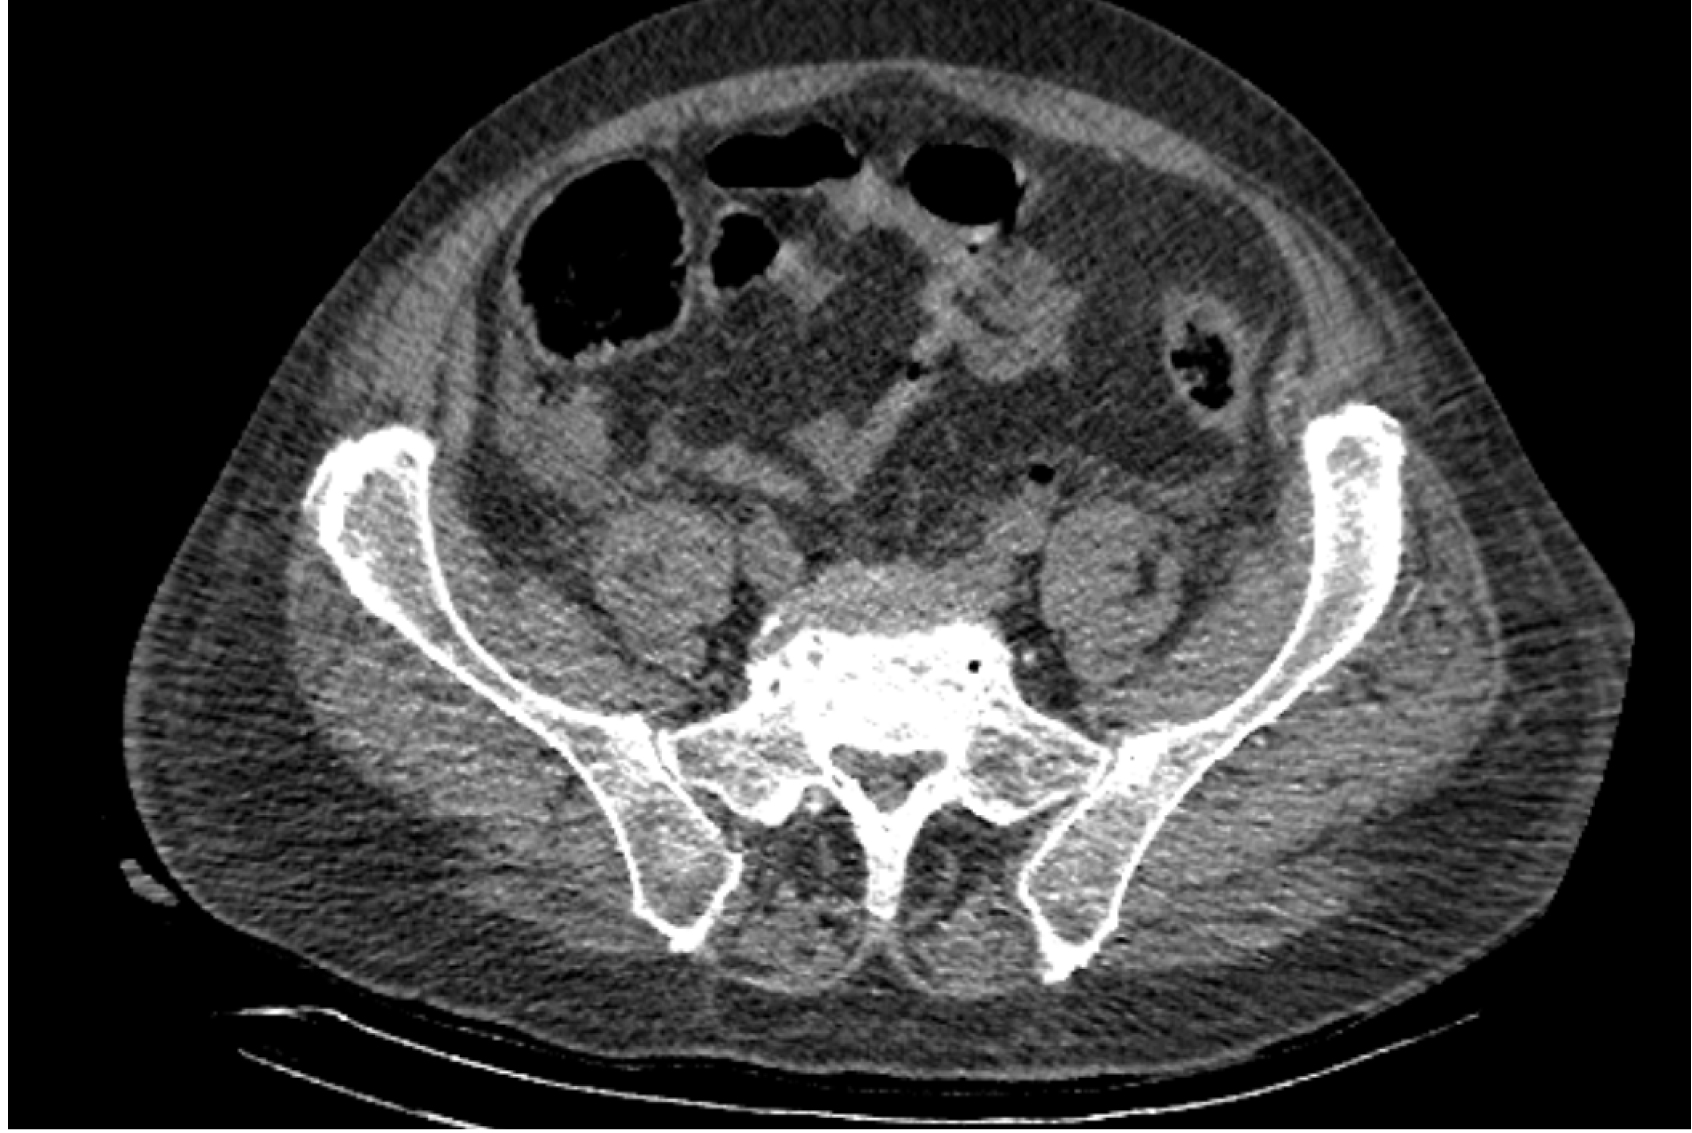

На следующий день состояние пациента оставалось тяжелым, с отрицательной динамикой, креатинин сыворотки возрос до 735,2 ммоль/л, Появились жалобы на слабость, тошноту. При осмотре: живот мягкий, вздут по всем отделам, при пальпации болезненный. Область почек не изменена, при пальпации безболезненна, патологических изменений в области почек не выявлено. Симптом поколачивания отрицательный билатерально. При УЗИ были обнаружены плевральный выпот по 300–400 мл с каждой стороны, гепатомегалия, увеличение размеров селезенки, асцит. Кроме того, в обеих почках были визуализированы тени, характерные для конкрементов. По данным компьютерной томографии (КТ) конкрементов не обнаружено, но в лоханке, на всем протяжении левого мочеточника и, частично, в правом мочеточнике, а также в мочевом пузыре визуализировался газ (рис. 1–6).

Рис. 1. Компьютерная томография органов брюшной полости, забрюшинного пространства, органов малого таза. Газ в мочевом пузыре

Рис. 2. Компьютерная томография органов брюшной полости, забрюшинного пространства, органов малого таза. Газ в мочевом пузыре

Рис. 3. Компьютерная томография органов брюшной полости, забрюшинного пространства, органов малого таза. Газ в левом мочеточнике